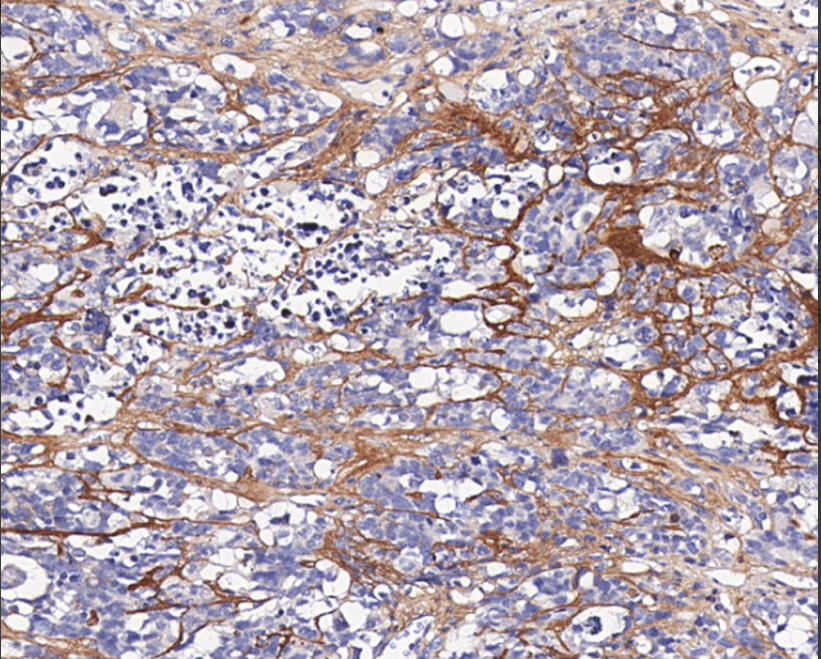

Cellular localization: cytoplasmic

Positive control: cartilage/chondrosarcoma

Type II collagen is a structural protein in the cartilage matrix that does not cross-react with types I, III, IV, V and VI collagen, as well as other human serum proteins or non-collagenous extracellular-associated proteins. It is mainly used for the study of type II collagen distribution.

Collagen II antibody reagents can specifically bind to Collagen II molecular antigens. Immunohistochemistry kits containing Collagen II antibody reagents are suitable for the precise diagnosis of benign and malignant tumors.